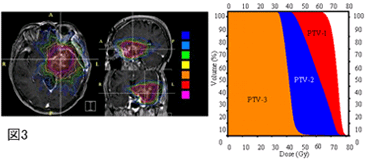

一方、IMRTのもう一つの特徴として、同時に異なる線量分布を作成できるSimultaneous Integrated Boostという照射法をあげることができます。例えば、腫瘍本体に強く照射を行い、その周囲に柔らかく照射を行うといったことが自由にできるのです(図3)。この照射法は特に浸潤性腫瘍において有効と思われ、千葉県がんセンターでは2002年から神経膠腫の治療にIMRTを応用し、優れた治療効果を証明しています。